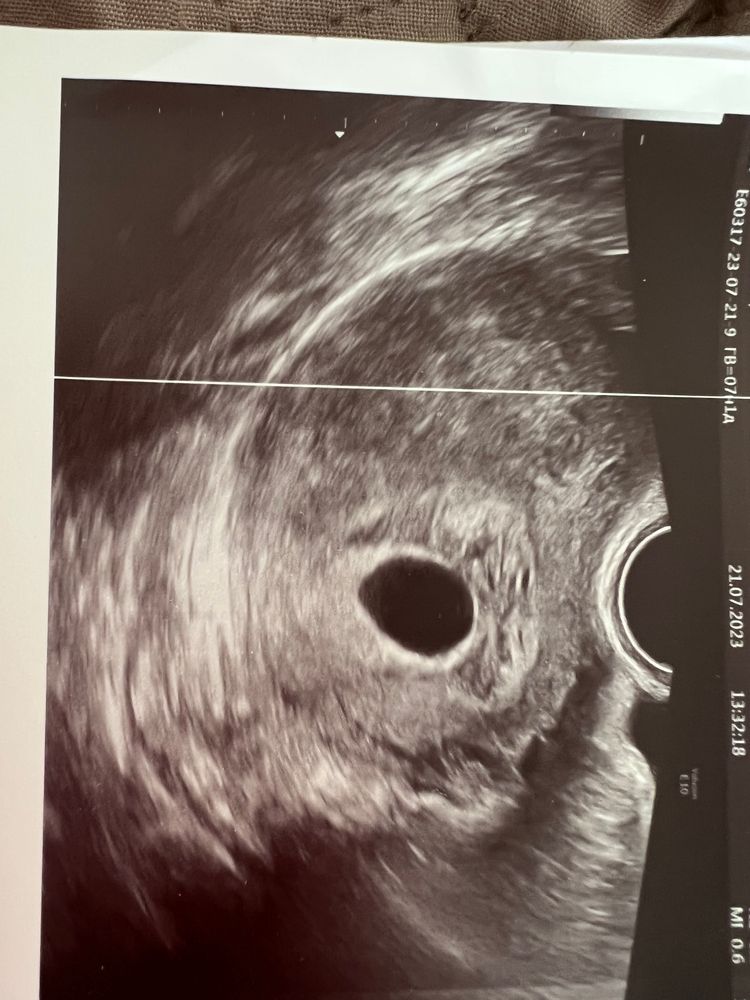

Девочки 7 акушерских недель , овуляция слева где нет трубы , в анамнезе и бх и внемотчные и тд , не долго я радовалась // сегодня два узиста подтвердили анэмбрионию , по первому узи Жм нет , пя 21, по второму жм нет пя 18 , буду готовится к прерыванию , хотели сегодня ( вернее направили ) решила подождать и отменила утрожестан , конец пришёл так и не успев начаться … нет слов….

Конечно, надежда умирает последней, но жм должен появиться до размеров пя в 16 мм. Это эмбрион ждут до 25.. скорее всего это анэмбриония. Увы(

Да скорее всего это анэмбриония. Но я бы подождала еще немного чтоб 100%, всякое в жизни бывает.

Если плодное яйцо меньше 25 мм, нужно ждать

Хотя бы ещё 7 дней

Вообще существует даже такой приказ, при отсутсвии эмбриона в ПЯ менее 25 мм - повторить Узи через 7-10 дней